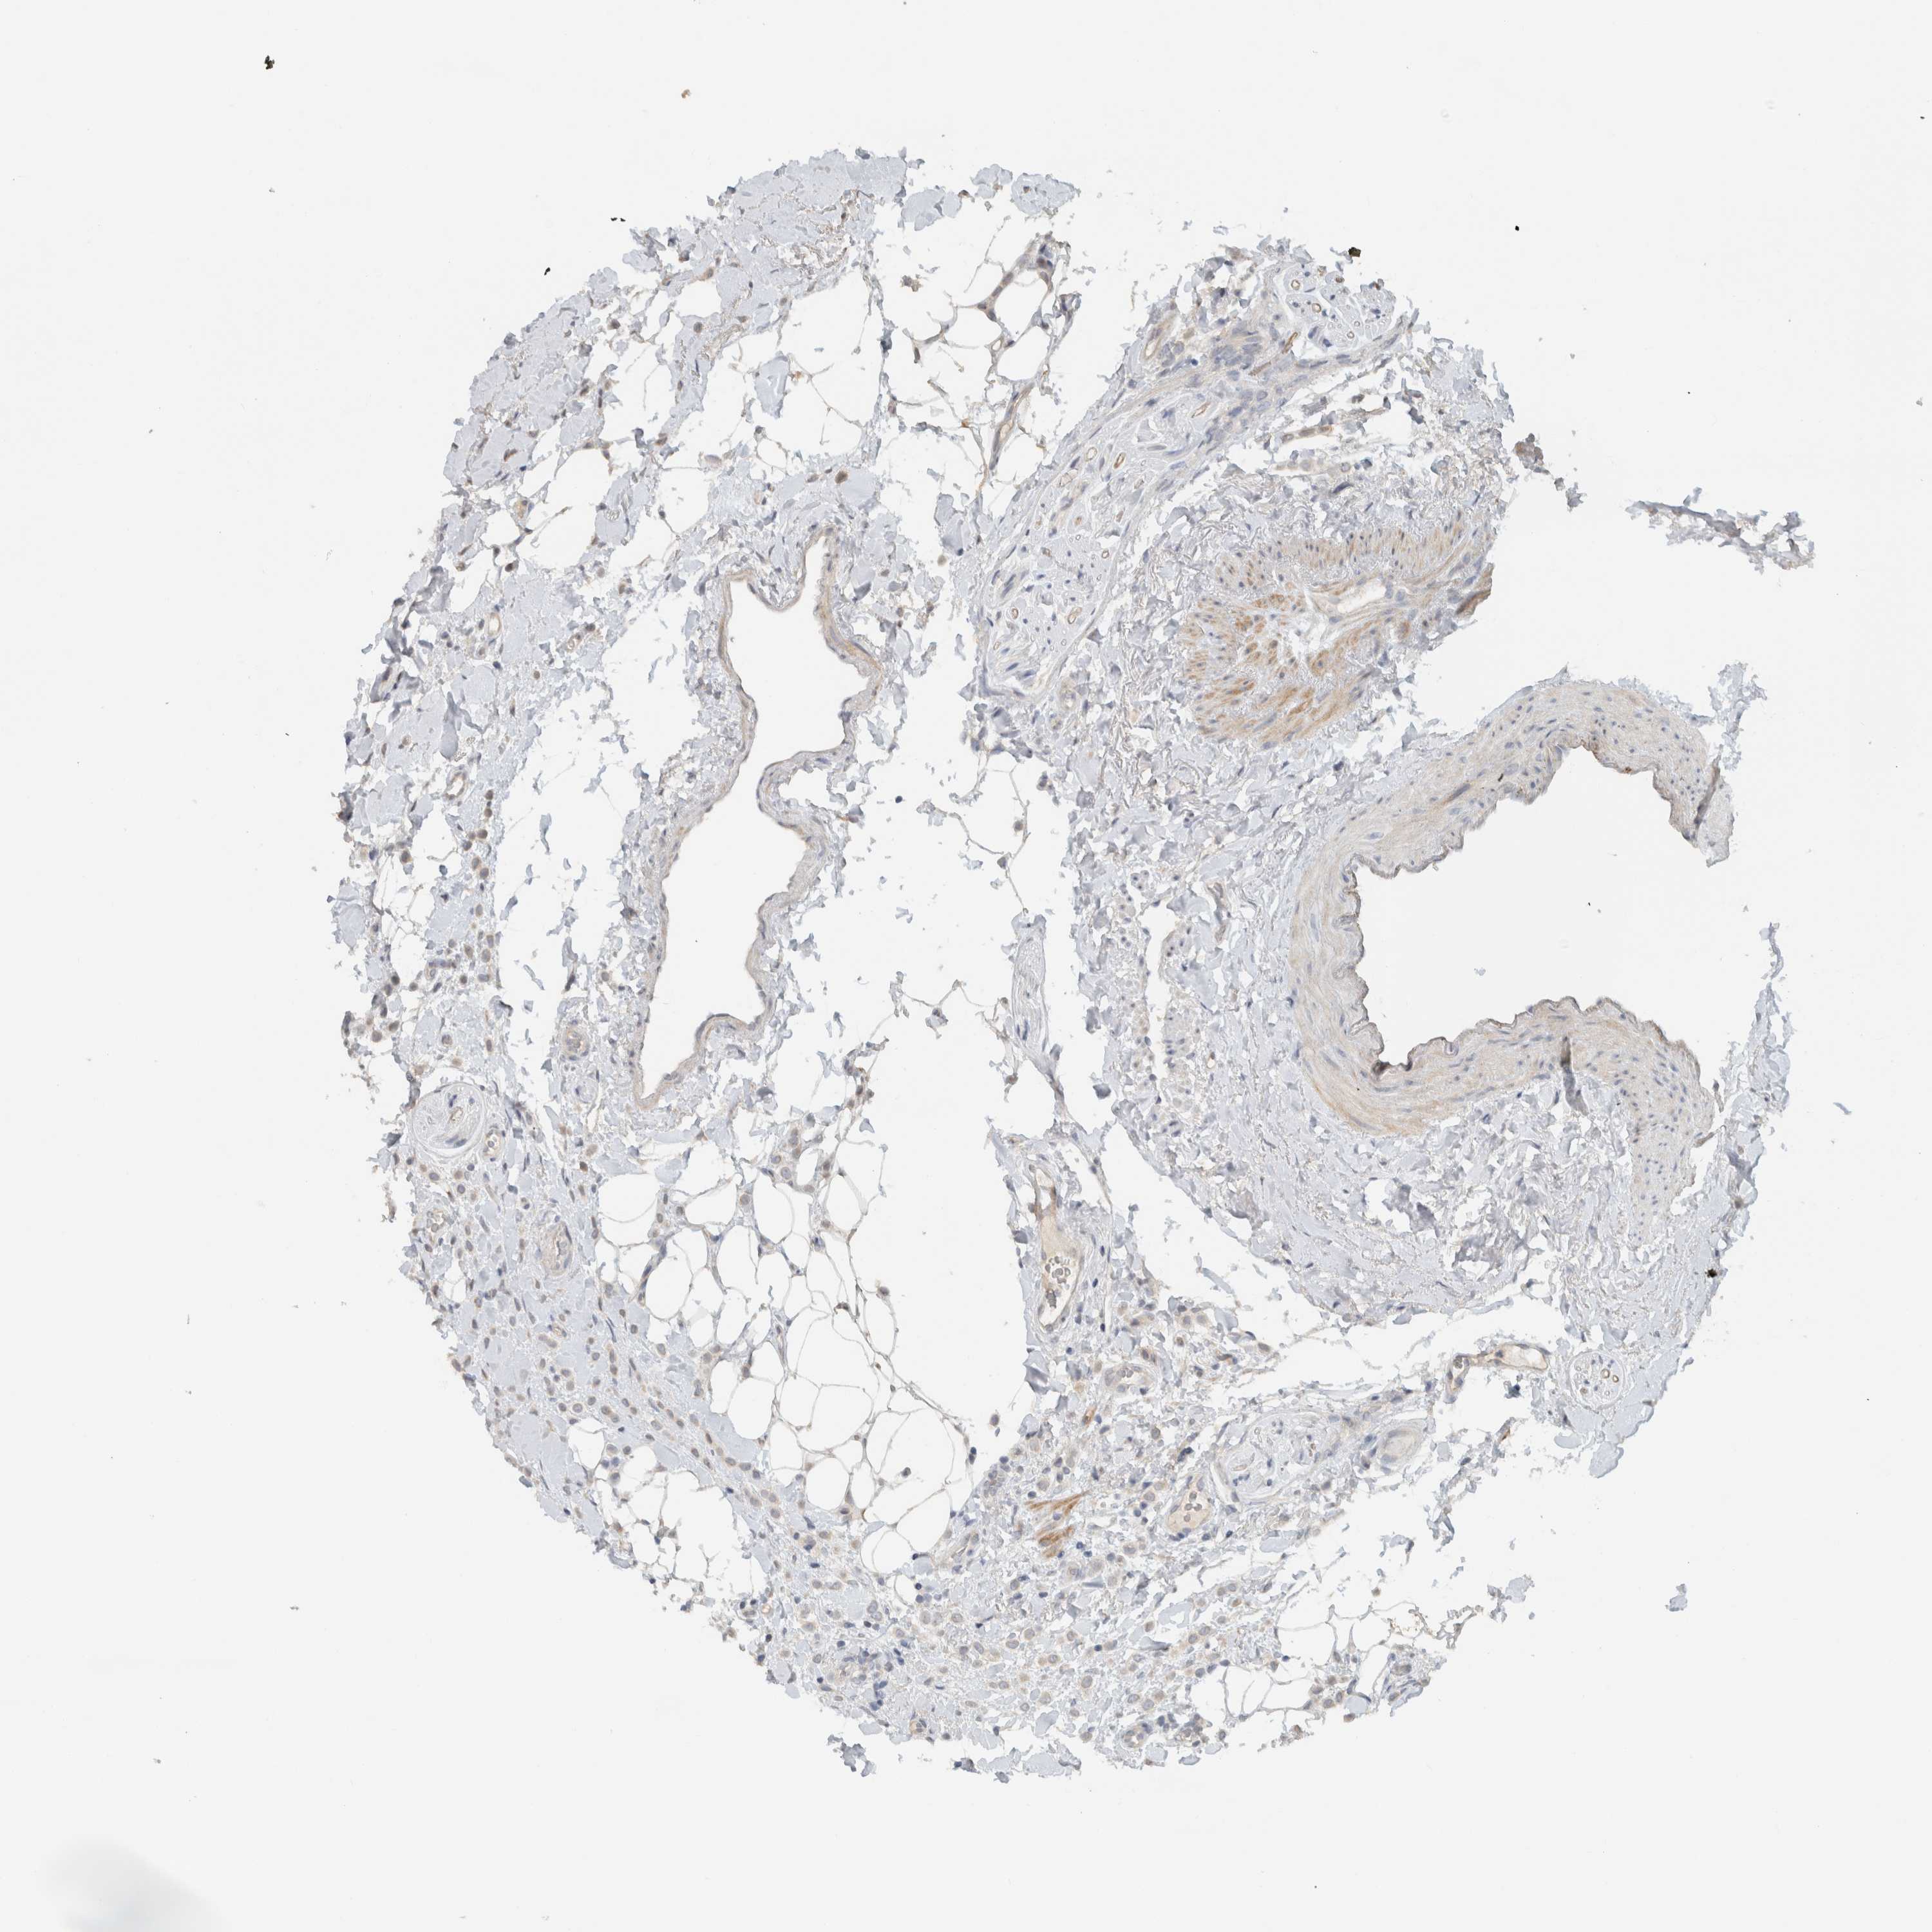

BRCA TCGA BRCA VALIDATION PROTEIN EXPRESSION